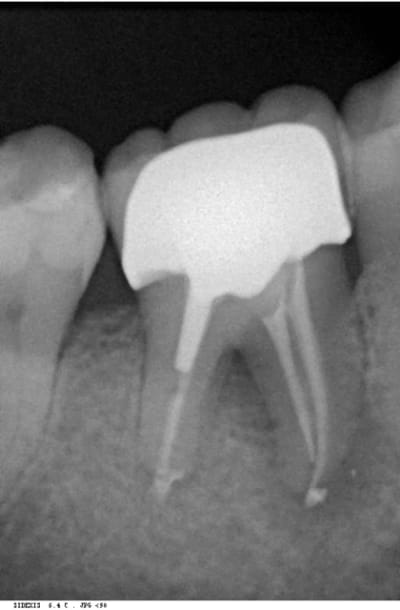

bon les pièces jointes d'alhoun.

décidément aussi nul en endo qu'en internet, et ton implant il est de traviole;)

Trev4 oye2tl - Eugenol

Trev5 lavbuq - Eugenol

Trev1 rgpu7x - Eugenol

Trev2 c5sddm - Eugenol

Trev3 wgcbda - Eugenol

dans la même philosophie de connectique

Easyimplant mjxotp - Eugenol

Rvg easy briwxo - Eugenol